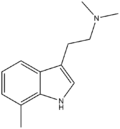

| Chemical structure | Short Name | Origin | Ring Substitution | RN1 | RN2 | Full Name | CAS Number |

|---|---|---|---|---|---|---|---|

| 4-Methyl-DMT | artificial | 4-CH3 | CH3 | CH3 | 4,N,N-trimethyltryptamine | 28289-23-8 |

| 7-Methyl-DMT | artificial | 7-CH3 | CH3 | CH3 | 7,N,N-trimethyltryptamine | 65882-39-5 |